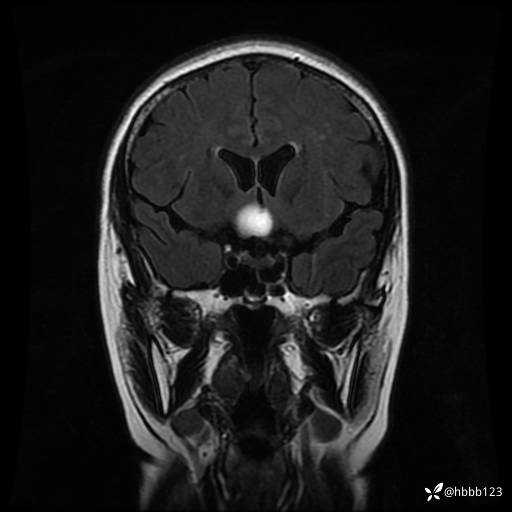

T2 Flair冠状位重建:

T1WI 增强 冠状位重建: